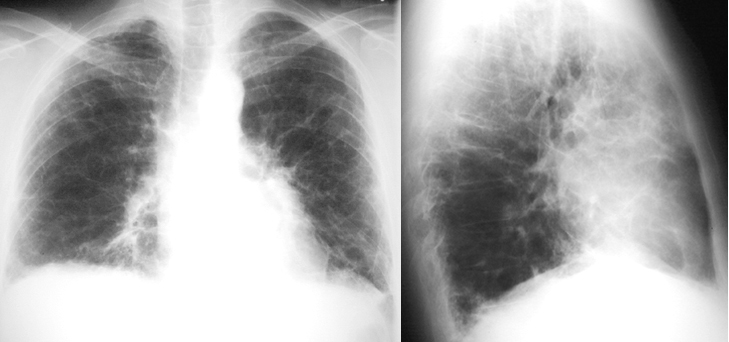

Rheumatoid Lung

Extensive bilateral interstitial fibrosis.